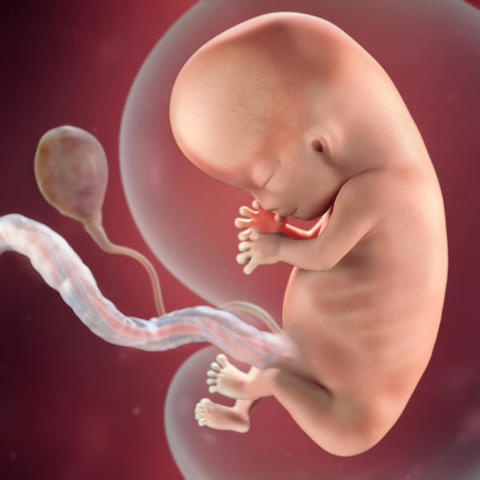

Al final de la segunda semana, si tienes ciclos regulares de 28 días, se produce la ovulación. El ovario produce un ovocito -mal denominado óvulo- que libera hacia la trompa de Falopio y será el futuro óvulo en caso de ser fecundado por un espermatozoide. Por tanto, denominamos óvulo al ovocito fecundado por un espermatozoide. El endometrio, las paredes del útero, comienzan a engrosarse preparándose para una posible implantación del óvulo.

Al grupo de células en continua multiplicación se le llama cigoto. De cigoto pasa a denominarse blastómera, luego mórula y posteriormente blastocisto. El blastocisto llega de la trompa de Falopio a la cavidad uterina y se implanta en la pared del útero una semana después de haberse producido la fecundación.

En la semana 3 de embarazo, el embrión es un grupo de células que se están multiplicando muy rápidamente dentro del útero materno y se llama cigoto. Tras la fecundación del ovocito por el espermatozoide, se fusionan los dos núcleos aportando cada uno 23 cromosomas con la dotación genética de ambos. Es decir tendra 46 cromosomas.

En la semana 4 se notaran 3 capas de la celula, que darán lugar a los futuros órganos: ectodermo, endodermo y mesodermo. El ectodermo dará lugar al sistema nervioso central; el endodermo al tracto gastrointestinal, páncreas, hígado y glándula tiroides; y el mesodermo, a los huesos, músculos y sistema sanguíneo. Se está formando la cavidad amniótica y en su interior el líquido amniótico. La placenta que es el encargado de llevar el oxígeno y los nutrientes de la madre al bebé.

El embrión se le dira haci hasta la semana 12 que se le llamara feto mide aproximadamente 1,25 milímetros.

El esqueleto del bebé se está empezando a formar en la semana 5 de gestación. Se esta desarollando el corazon.